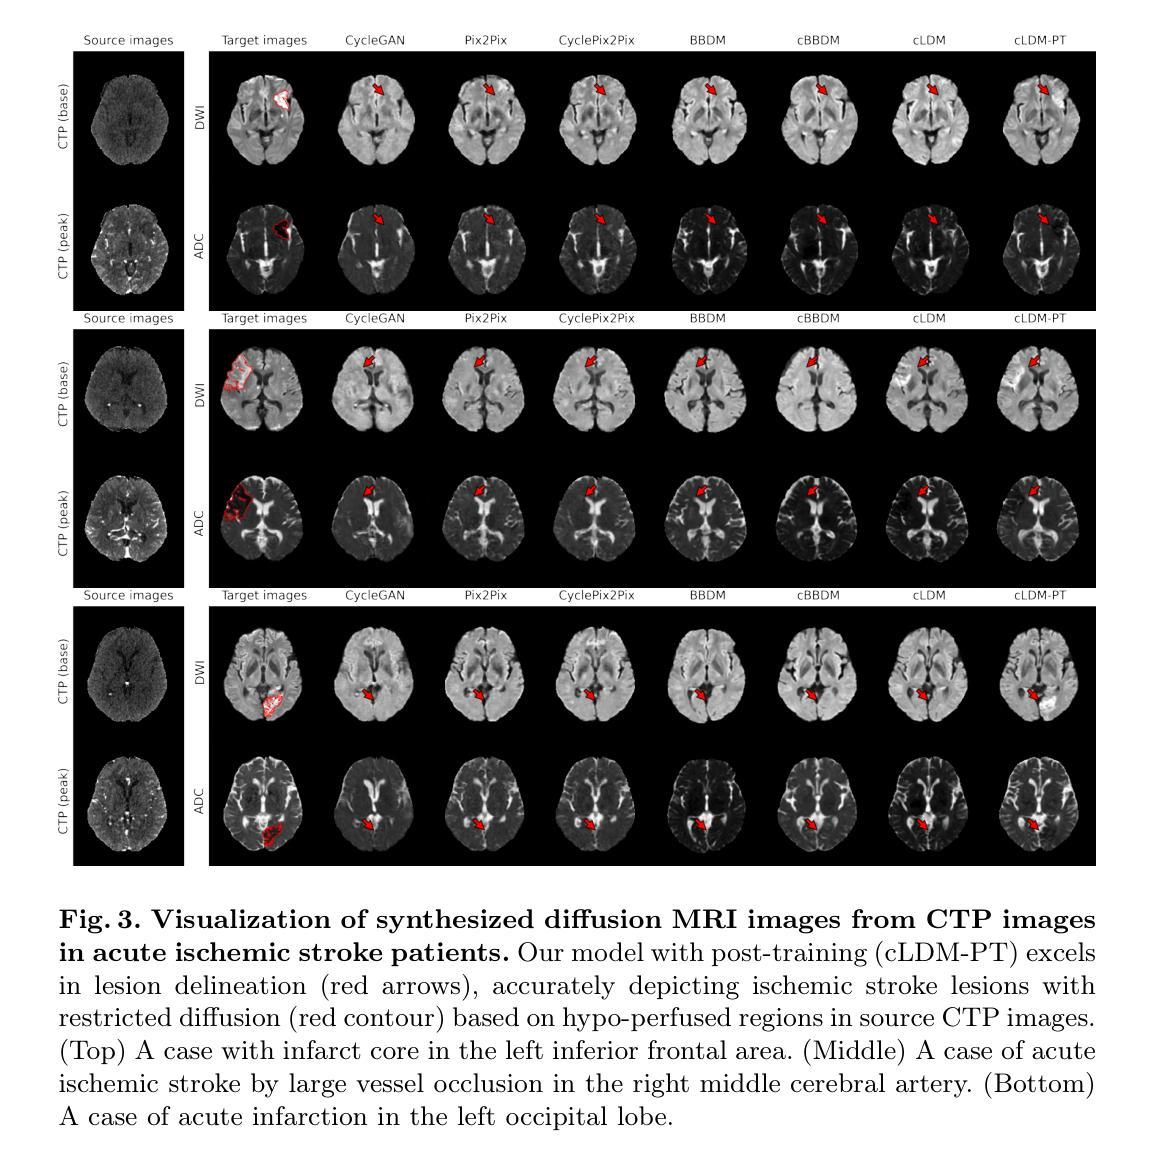

Lesion-Aware Post-Training of Latent Diffusion Models for Synthesizing Diffusion MRI from CT Perfusion

Authors:Junhyeok Lee, Hyunwoong Kim, Hyungjin Chung, Heeseong Eom, Joon Jang, Chul-Ho Sohn, Kyu Sung Choi

Image-to-Image translation models can help mitigate various challenges inherent to medical image acquisition. Latent diffusion models (LDMs) leverage efficient learning in compressed latent space and constitute the core of state-of-the-art generative image models. However, this efficiency comes with a trade-off, potentially compromising crucial pixel-level detail essential for high-fidelity medical images. This limitation becomes particularly critical when generating clinically significant structures, such as lesions, which often occupy only a small portion of the image. Failure to accurately reconstruct these regions can severely impact diagnostic reliability and clinical decision-making. To overcome this limitation, we propose a novel post-training framework for LDMs in medical image-to-image translation by incorporating lesion-aware medical pixel space objectives. This approach is essential, as it not only enhances overall image quality but also improves the precision of lesion delineation. We evaluate our framework on brain CT-to-MRI translation in acute ischemic stroke patients, where early and accurate diagnosis is critical for optimal treatment selection and improved patient outcomes. While diffusion MRI is the gold standard for stroke diagnosis, its clinical utility is often constrained by high costs and low accessibility. Using a dataset of 817 patients, we demonstrate that our framework improves overall image quality and enhances lesion delineation when synthesizing DWI and ADC images from CT perfusion scans, outperforming existing image-to-image translation models. Furthermore, our post-training strategy is easily adaptable to pre-trained LDMs and exhibits substantial potential for broader applications across diverse medical image translation tasks.